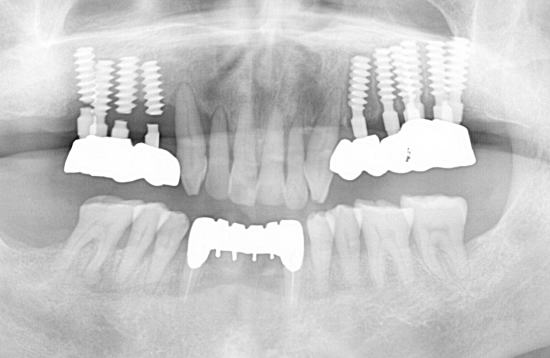

右上インプラント破折。このままインプラントを撤去すると、骨や歯肉の喪失が多くなるので、補綴物だけ外して、垂直+頬舌方向に骨造成を行う。

骨造成を行ってから、インプラントを撤去。骨幅が大きくなっているので、従来のインプラントより直径の太い物を植立して、破折防止。

破折したインプラントを除去すると、骨の喪失が大きくなるので、撤去する前に造骨してから撤去すると、その後には、従来のインプラントより直径の大きいインプラントが可能になります。